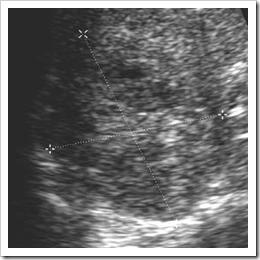

Ultrasound images of Vascular abnormalities of the spleen

Ultrasound images Splenic infarct Splenic infarction is most commonly associated with endocarditis, sickle cell disease and myeloproliferative disorders11 and also with lymphoma andcancers. It usually results from thrombosis of one or more of the splenic artery branches. Because the spleen is supplied by both the splenic and gastric arteries, infarction tends to be segmental rather than global. Patients may present with LUQ pain, but not invariably. Initially the area of infarction is hypoechoic and usually wedge-shaped, solitary and extending to the periphery of the spleen (Fig. A and B). The lesion may decrease in time, and gradually fibrose, becoming hyperechoic. It demonstrates a lack of Doppler perfusion compared with the normal splenic tissue. In rare cases of total splenic infarction (Fig.C), due to occlusion of the proximal main splenic artery, greyscale sonographic appearances may be normal in the early stages. Although the lack of colour Doppler flow may assist in the diagnosis, CT is the method of choice. Occasionally infarcts may become infected or may haemorrhage. Sonography can successfully document such complications and is used to monitor their resolution serially. In patients with multiple infarcts, such as those with sickle-cell disease, the spleen may become scarred, giving rise to a patchy, heterogeneous texture.

ultrasound images Splenic infarct due to an embolus following recent liver resection

fig. B

Ultrasound images of Colour Doppler of the same

patient demonstrates a lack of perfusion in the infarcted area